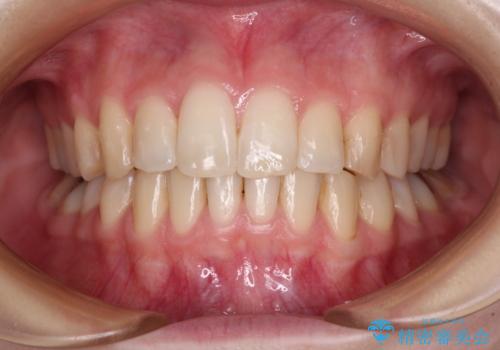

前歯のクロスバイトと治療が必要なむし歯 矯正とセラミックの総合歯科治療